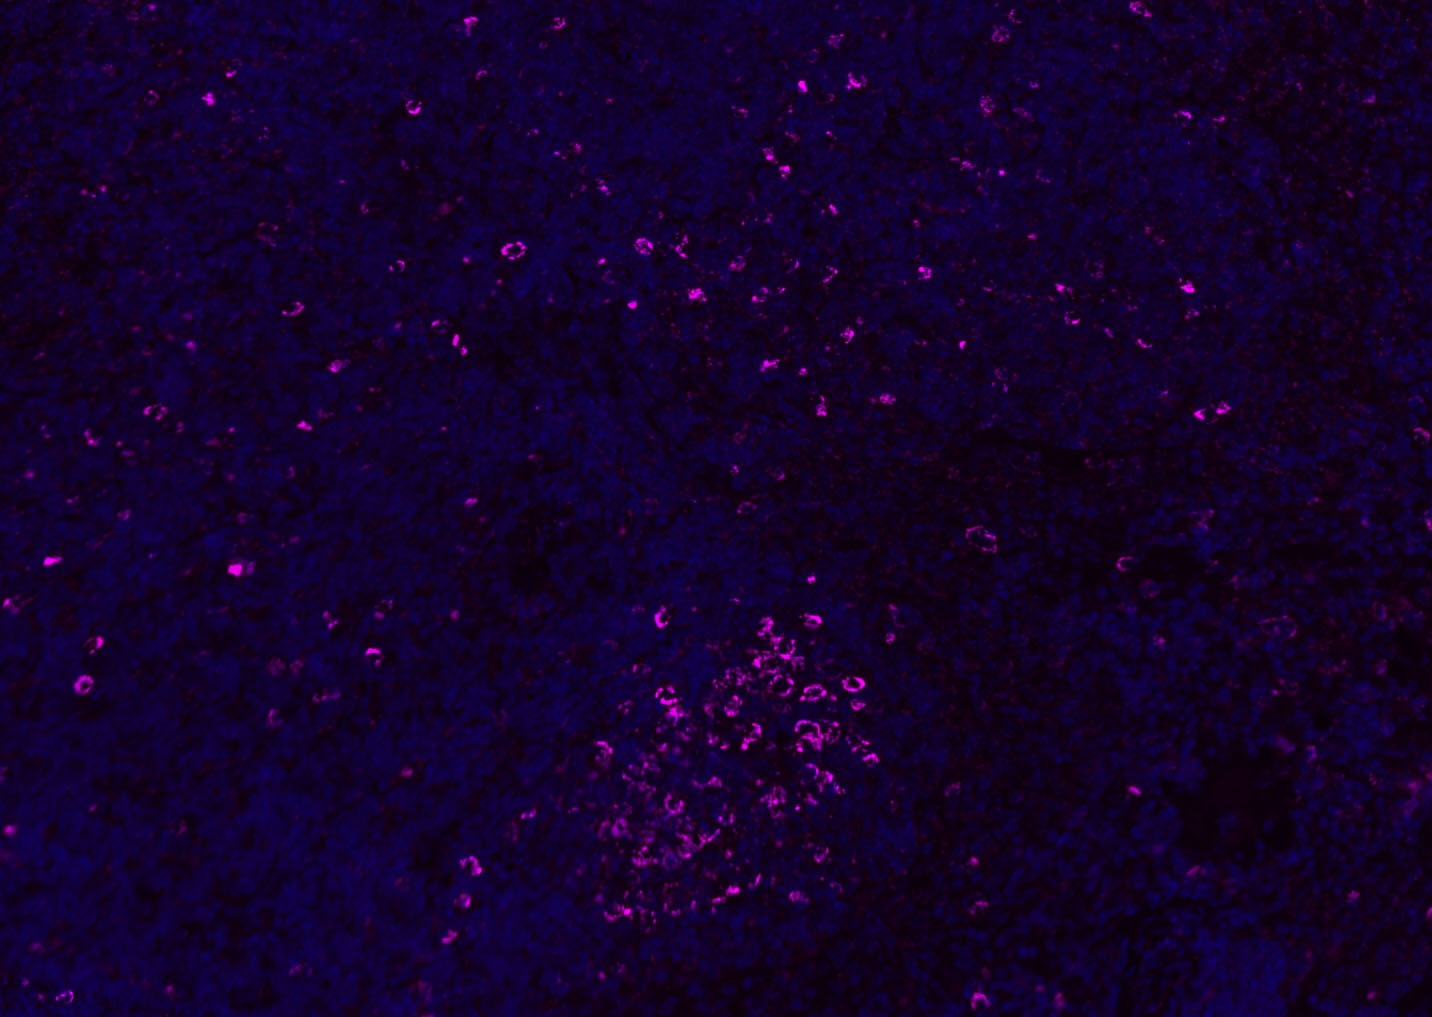

| Verified Activity | 1. Tissue/cell: human lung carcinoma;4% Paraformaldehyde-fixed and paraffin-embedded; Antigen retrieval: citrate buffer (0.01M, pH6.0), Boiling bathing for 15 min; Blocking buffer (normal goat serum) at 37°C for 20 min; Incubation: Anti-CD8 Polyclonal Antibody, Unconjugated (TMAB-00392) 1:200, overnight at 4°C; The secondary antibody was Goat Anti-Rabbit IgG, Cy3 conjugated used at 1:200 dilution for 40 minutes at 37°C. DAPI (5 μg/ml,blue) was used to stain the cell nucleus. 2. Paraformaldehyde-fixed, paraffin embedded (mouse lymphoid); Antigen retrieval by boiling in sodium citrate buffer (pH6.0) for 15 min; Blocking buffer (normal goat serum) at 37°C for 30 min; Antibody incubation with (CD8B) Polyclonal Antibody, Unconjugated (TMAB-00392) at 1:200 overnight at 4°C, followed by a conjugated Goat Anti-Rabbit IgG antibody for 90 minutes, and DAPI for nucleus staining. 3. Paraformaldehyde-fixed, paraffin embedded (rat spleen); Antigen retrieval by boiling in sodium citrate buffer (pH6.0) for 15 min; Blocking buffer (normal goat serum) at 37°C for 30 min; Antibody incubation with (CD8B) Polyclonal Antibody, Unconjugated (TMAB-00392) at 1:200 overnight at 4°C, followed by a conjugated Goat Anti-Rabbit IgG antibody for 90 minutes, and DAPI for nucleus staining. 4. Paraformaldehyde-fixed, paraffin embedded (mouse thymus); Antigen retrieval by boiling in sodium citrate buffer (pH6.0) for 15 min; Blocking buffer (normal goat serum) at 37°C for 30 min; Antibody incubation with (CD8B) Polyclonal Antibody, Unconjugated (TMAB-00392) at 1:200 overnight at 4°C, followed by a conjugated Goat Anti-Rabbit IgG antibody for 90 minutes, and DAPI for nucleus staining. 5. Paraformaldehyde-fixed, paraffin embedded (rat lymphoid); Antigen retrieval by boiling in sodium citrate buffer (pH6.0) for 15 min; Blocking buffer (normal goat serum) at 37°C for 30 min; Antibody incubation with (CD8B) Polyclonal Antibody, Unconjugated (TMAB-00392) at 1:200 overnight at 4°C, followed by a conjugated Goat Anti-Rabbit IgG antibody for 90 minutes, and DAPI for nucleus staining. 6. Paraformaldehyde-fixed, paraffin embedded (rat thymus); Antigen retrieval by boiling in sodium citrate buffer (pH6.0) for 15 min; Blocking buffer (normal goat serum) at 37°C for 30 min; Antibody incubation with (CD8B) Polyclonal Antibody, Unconjugated (TMAB-00392) at 1:200 overnight at 4°C, followed by a conjugated Goat Anti-Rabbit IgG antibody for 90 minutes, and DAPI for nucleus staining. 7. Paraformaldehyde-fixed, paraffin embedded (human tonsil); Antigen retrieval by boiling in sodium citrate buffer (pH6.0) for 15 min; Blocking buffer (normal goat serum) at 37°C for 30 min; Antibody incubation with (CD8B) Polyclonal Antibody, Unconjugated (TMAB-00392) at 1:200 overnight at 4°C, followed by a conjugated Goat Anti-Rabbit IgG antibody for 90 minutes, and DAPI for nucleus staining. 8. Paraformaldehyde-fixed, paraffin embedded (mouse lymphoid); Antigen retrieval by boiling in sodium citrate buffer (pH6.0) for 15 min; Blocking buffer (normal goat serum) at 37°C for 30 min; Antibody incubation with (CD8B) Polyclonal Antibody, Unconjugated (TMAB-00392) at 1:200 overnight at 4°C, followed by a conjugated Goat Anti-Rabbit IgG antibody for 90 minutes, and DAPI for nucleus staining. 9. Paraformaldehyde-fixed, paraffin embedded (rat thymus); Antigen retrieval by boiling in sodium citrate buffer (pH6.0) for 15 min; Blocking buffer (normal goat serum) at 37°C for 30 min; Antibody incubation with (CD8B) Polyclonal Antibody, Unconjugated (TMAB-00392) at 1:200 overnight at 4°C, followed by a conjugated Goat Anti-Rabbit IgG antibody for 90 minutes, and DAPI for nucleus staining. 10. Paraformaldehyde-fixed, paraffin embedded (human tonsil); Antigen retrieval by boiling in sodium citrate buffer (pH6.0) for 15 min; Blocking buffer (normal goat serum) at 37°C for 30 min; Antibody incubation with (CD8B) Polyclonal Antibody, Unconjugated (TMAB-00392) at 1:200 overnight at 4°C, followed by a conjugated Goat Anti-Rabbit IgG antibody for 90 minutes, and DAPI for nucleus staining. 11. Paraformaldehyde-fixed, paraffin embedded (mouse spleen); Antigen retrieval by boiling in sodium citrate buffer (pH6.0) for 15 min; Blocking buffer (normal goat serum) at 37°C for 30 min; Antibody incubation with (CD8B) Polyclonal Antibody, Unconjugated (TMAB-00392) at 1:200 overnight at 4°C, followed by a conjugated Goat Anti-Rabbit IgG antibody for 90 minutes, and DAPI for nucleus staining. 12. Paraformaldehyde-fixed, paraffin embedded (rat lymphoid); Antigen retrieval by boiling in sodium citrate buffer (pH6.0) for 15 min; Blocking buffer (normal goat serum) at 37°C for 30 min; Antibody incubation with (CD8B) Polyclonal Antibody, Unconjugated (TMAB-00392) at 1:200 overnight at 4°C, followed by a conjugated Goat Anti-Rabbit IgG antibody for 90 minutes, and DAPI for nucleus staining. 13. Paraformaldehyde-fixed, paraffin embedded (Rat lymphoid); Antigen retrieval by boiling in sodium citrate buffer (pH6.0) for 15 min; Blocking buffer (normal goat serum) at 37°C for 30 min; Antibody incubation with (CD8B) Polyclonal Antibody, Unconjugated (TMAB-00392) at 1:100 overnight at 4°C, followed by a conjugated Goat Anti-Rabbit IgG antibody for 90 minutes, and DAPI for nucleus staining. 14. Paraformaldehyde-fixed, paraffin embedded (mouse thymus); Antigen retrieval by boiling in sodium citrate buffer (pH6.0) for 15 min; Blocking buffer (normal goat serum) at 37°C for 30 min; Antibody incubation with (CD8B) Polyclonal Antibody, Unconjugated (TMAB-00392) at 1:100 overnight at 4°C, followed by a conjugated Goat Anti-Rabbit IgG antibody for 90 minutes, and DAPI for nucleus staining. 15. Paraformaldehyde-fixed, paraffin embedded (mouse spleen); Antigen retrieval by boiling in sodium citrate buffer (pH6.0) for 15 min; Blocking buffer (normal goat serum) at 37°C for 30 min; Antibody incubation with (CD8B) Polyclonal Antibody, Unconjugated (TMAB-00392) at 1:100 overnight at 4°C, followed by a conjugated Goat Anti-Rabbit IgG antibody for 90 minutes, and DAPI for nucleus staining. 16. Paraformaldehyde-fixed, paraffin embedded (rat spleen); Antigen retrieval by boiling in sodium citrate buffer (pH6.0) for 15 min; Blocking buffer (normal goat serum) at 37°C for 30 min; Antibody incubation with (CD8B) Polyclonal Antibody, Unconjugated (TMAB-00392) at 1:100 overnight at 4°C, followed by a conjugated Goat Anti-Rabbit IgG antibody for 90 minutes, and DAPI for nucleus staining. 17. Paraformaldehyde-fixed, paraffin embedded (rat thymus); Antigen retrieval by boiling in sodium citrate buffer (pH6.0) for 15 min; Blocking buffer (normal goat serum) at 37°C for 30 min; Antibody incubation with (CD8B) Polyclonal Antibody, Unconjugated (TMAB-00392) at 1:100 overnight at 4°C, followed by a conjugated Goat Anti-Rabbit IgG antibody for 90 minutes, and DAPI for nucleus staining. 18. Paraformaldehyde-fixed, paraffin embedded (human tonsil); Antigen retrieval by boiling in sodium citrate buffer (pH6.0) for 15 min; Blocking buffer (normal goat serum) at 37°C for 30 min; Antibody incubation with (CD8B) Polyclonal Antibody, Unconjugated (TMAB-00392) at 1:100 overnight at 4°C, followed by a conjugated Goat Anti-Rabbit IgG antibody for 90 minutes, and DAPI for nucleus staining. 19. Paraformaldehyde-fixed, paraffin embedded (mouse lymphoid); Antigen retrieval by boiling in sodium citrate buffer (pH6.0) for 15 min; Blocking buffer (normal goat serum) at 37°C for 30 min; Antibody incubation with (CD8B) Polyclonal Antibody, Unconjugated (TMAB-00392) at 1:100 overnight at 4°C, followed by a conjugated Goat Anti-Rabbit IgG antibody for 90 minutes, and DAPI for nucleus staining. ![]() ![]() ![]() ![]() ![]() ![]() ![]() ![]() ![]() ![]() ![]() ![]() ![]() ![]() ![]() ![]() ![]() ![]() ![]() |